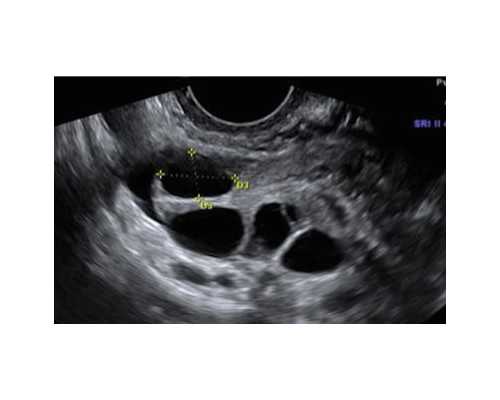

新疆助孕试管助孕服务主要包括取出女性的卵子和男性的精子进行体外受精,并将受精卵培养到一定程度后再移植到女性子宫内。这种技术可以有效解决因女性输卵管问题、男性精液质量不佳或其他原因导致的不孕不育问题。